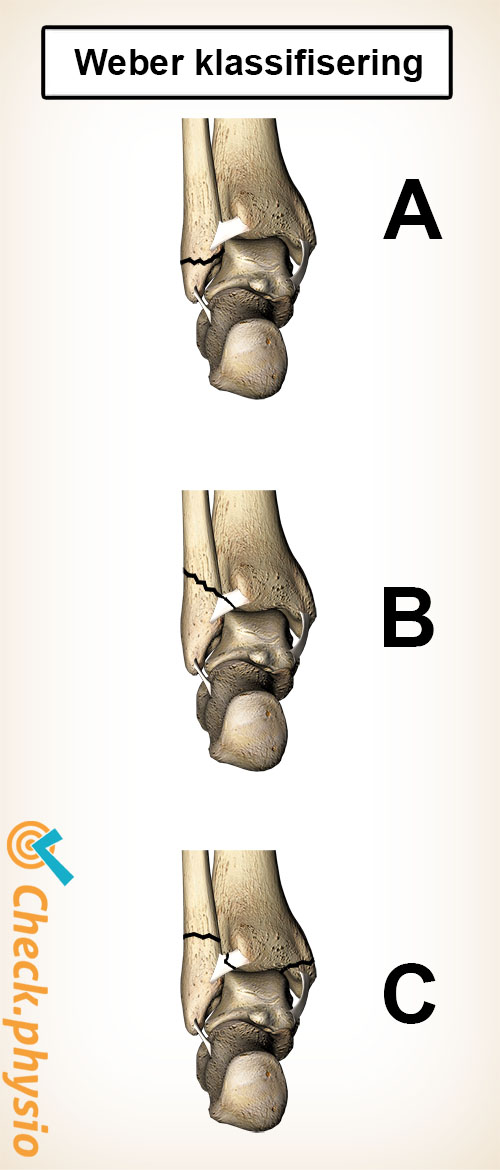

En mye brukt inndeling av brudd er den såkalte Weber-klassifiseringen. Den vurderer bruddets plassering. Dette er viktig, fordi det mellom fibula og tibia finnes en bindevevstruktur (kalt syndesmose). Klassifiseringen angir om denne også er revet over eller ikke.

- Weber A: Et lavt brudd i fibula, syndesmosen er intakt.

- Weber B: Et brudd i fibula på høyde med syndesmosen, som sannsynligvis også er (delvis) revet.

- Weber C: Et høyere brudd i fibula hvor syndesmosen også er revet. Det kan også være et brudd i tibia.